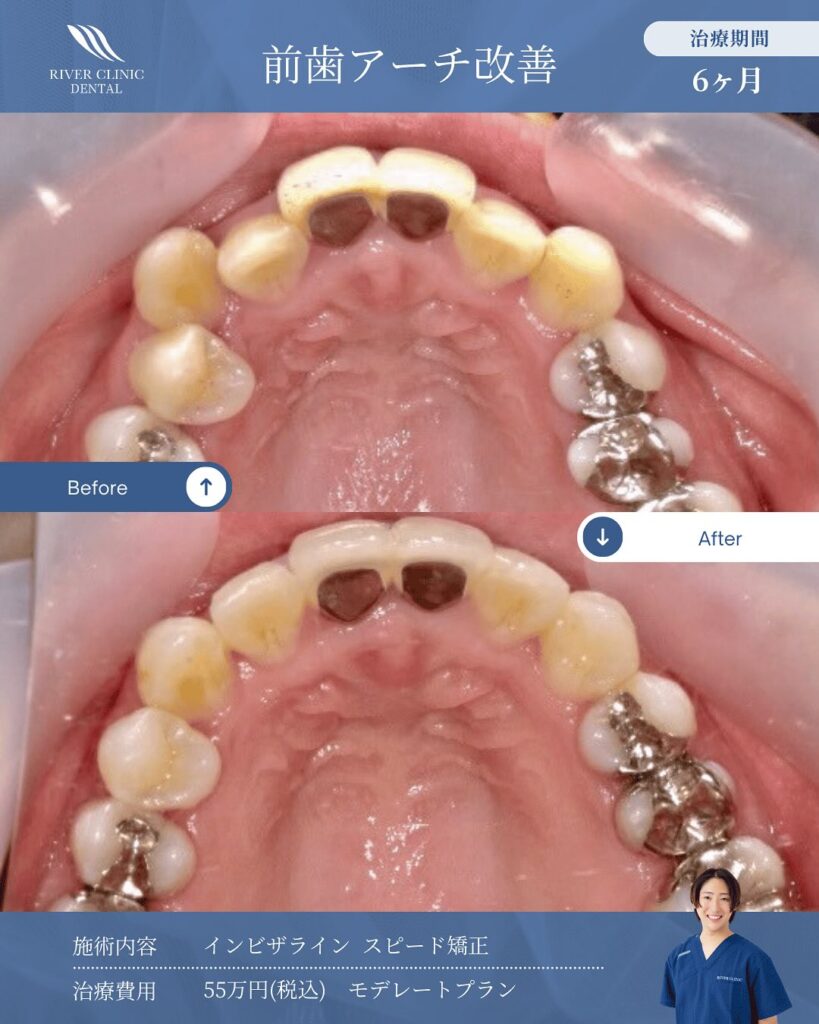

他院で1年以上はかかると言われても半年でアーチ改善して綺麗な歯並びになります💪

当院ではインビザラインという矯正治療システムを推奨しています。矯正期間が従来の矯正方法よりも短く、気軽にできるマウスピース型のものです。

| モデレートプラン(26枚コース) | 総額 500,000円(税込550,000円) 月々 5,000円(税込5,500円)(120回払い) |